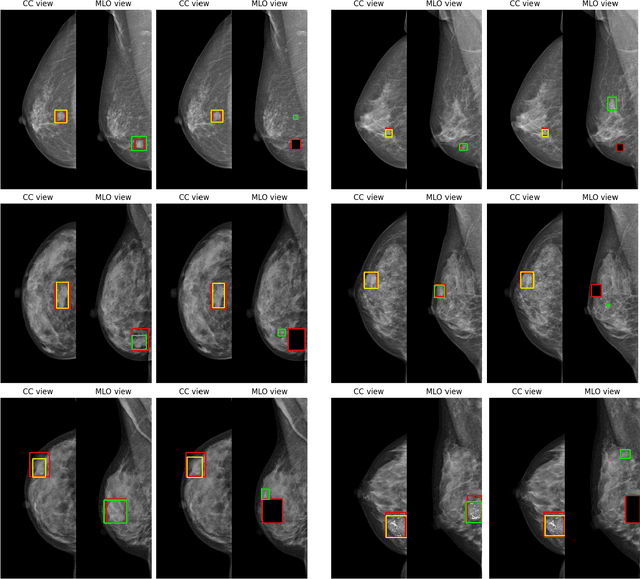

Screening mammography is the most widely used method for early breast cancer detection, significantly reducing mortality rates. The integration of information from multi-view mammograms enhances radiologists' confidence and diminishes false-positive rates since they can examine on dual-view of the same breast to cross-reference the existence and location of the lesion. Inspired by this, we present TransReg, a Computer-Aided Detection (CAD) system designed to exploit the relationship between craniocaudal (CC), and mediolateral oblique (MLO) views. The system includes cross-transformer to model the relationship between the region of interest (RoIs) extracted by siamese Faster RCNN network for mass detection problems. Our work is the first time cross-transformer has been integrated into an object detection framework to model the relation between ipsilateral views. Our experimental evaluation on DDSM and VinDr-Mammo datasets shows that our TransReg, equipped with SwinT as a feature extractor achieves state-of-the-art performance. Specifically, at the false positive rate per image at 0.5, TransReg using SwinT gets a recall at 83.3% for DDSM dataset and 79.7% for VinDr-Mammo dataset. Furthermore, we conduct a comprehensive analysis to demonstrate that cross-transformer can function as an auto-registration module, aligning the masses in dual-view and utilizing this information to inform final predictions. It is a replication diagnostic workflow of expert radiologists